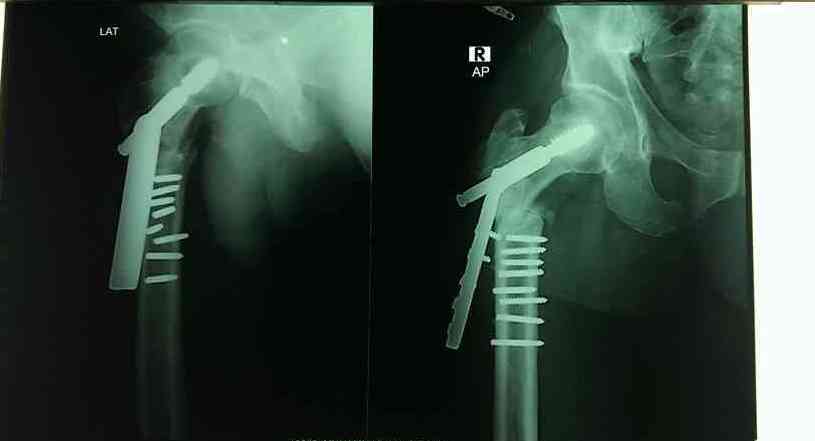

Pathological fracture, hip, unsp, init. A refill or prescription for pain. It covers icd codes 800 to 999.

Pathological Fracture, Hip, Unsp, Init.

Diseases of the digestive system. The icd code s720 is used to code hip fracture a hip fracture is a serious femoral fracture that occurs in the proximal end of the femur (the long bone running through the thigh), near the hip. Search about 41 items found relating to hip fracture

821 fracture of other and unspecified parts of femur; The icd code s720 is used to code hip fracture a hip fracture is a serious femoral fracture that occurs in the proximal end of the femur (the long bone running through the thigh), near the hip.